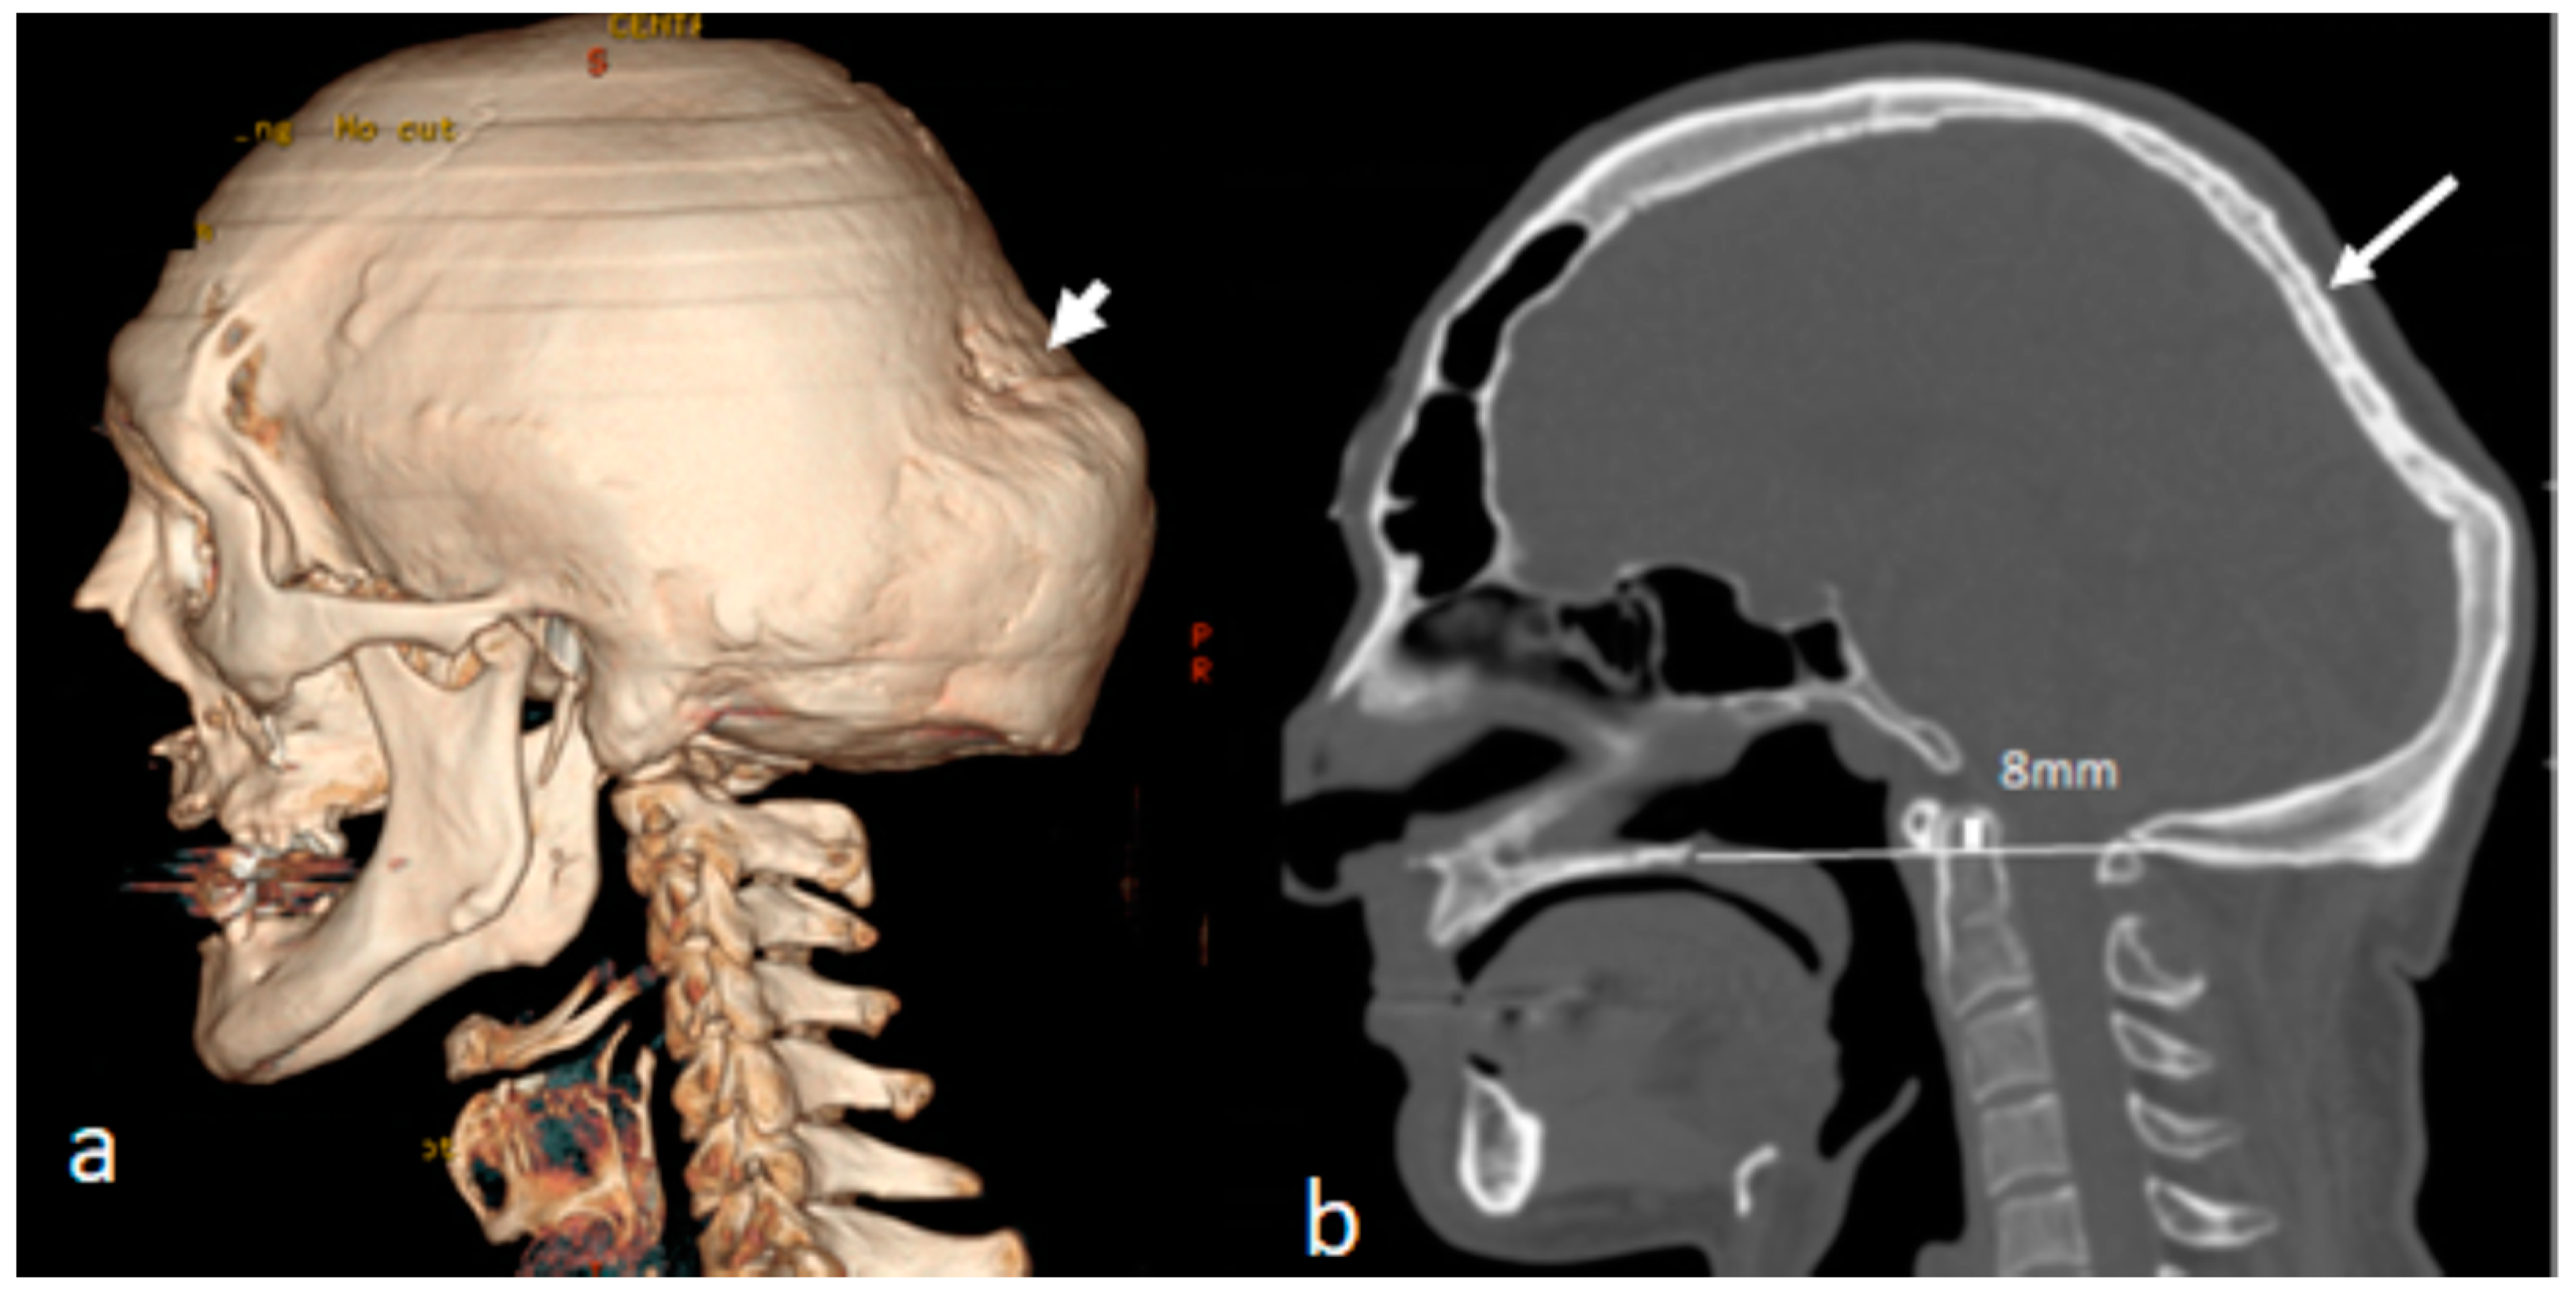

Patients with Osteogenesis Imperfecta Type IVB

4. Multicentric Carpotarsal Osteolysis Syndrome